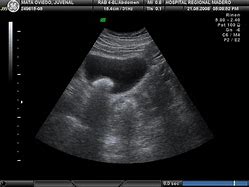

Cálculo Vesical

O tamanho dos cálculos vesicais e sua quantidade variam. Pode haver várias pedras ou apenas uma. Elas podem ser muito pequenas ou então grandes o suficiente para ocuparem quase toda a bexiga.

Seu aspecto também pode variar de uma pedra mole à uma extremamente dura; sua superfície pode ser mais lisa ou com maior quantidade de imperfeições

Além disso, elas podem ser móveis, que é o que ocorre na maior parte dos casos, ou serem fixas a alguma superfície da bexiga.